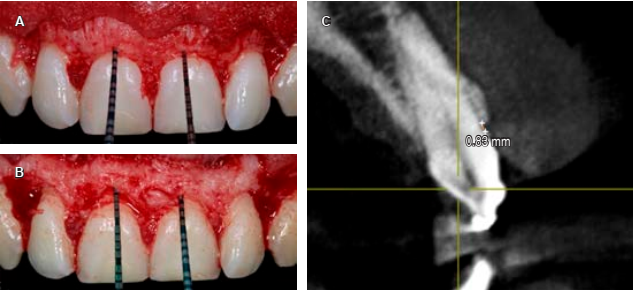

Se tomó la decisión de realizar la osteotomía y osteoplastia con el objetivo de dar el espacio al tejido supracrestal o espacio biológico (Tabla 5) (Figura 7A y B) y así permitir una inserción del tejido conectivo y epitelio de unión; se tomó la referencia de Gargiulo y colaboradores donde el espacio biológico está formado por 0.97 mm de epitelio de unión y 1.07 mm de tejido conectivo, sumando 2.04 mm.14

Figura 7 A) Medición de la cresta ósea a la unión cemento-esmalte con una sonda periodontal. B) Ostectomía realizada y medida con una sonda periodontal. C) Vista transversal en cone-beam computed tomography de pieza 2.1 con la distancia (0.83 mm) de la unión cemento-esmalte a cresta ósea.